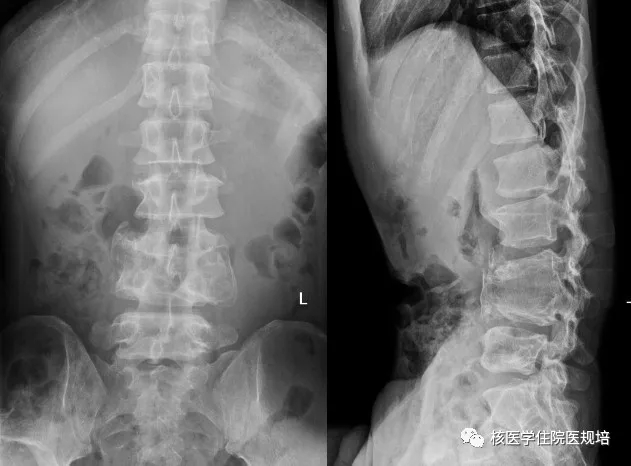

患者男性,30岁, 3个月前无明显诱因突发大小便失禁,同时伴下肢活动障碍,为进一步诊治就诊于我院。既往史:出生后诊断为先天性无痛无汗症,其他无特殊病史。查体:患者轮椅进入病房,神志清楚,对答切题;全身皮肤干燥、见多处瘢痕,皮肤痛觉缺失,指甲发育不良,脊柱生理屈度存在,无明显棘突压痛。双上肢未见明显畸形,肌力、肌张力未见明显异常。左下肢可见膝关节不规则隆起,表面不光滑,质硬,无波动感,关节屈伸正常,局部皮温正常,无皮肤红肿、破溃或静脉怒张,压痛(-);右下肢未见明显异常。双下肢感觉较弱,巴氏征(-)。实验室检查无明显异常发现。腰椎X光片及CT(图1.2)检查发现腰椎退行性变,L3、L4椎体融合,骨小梁结构模糊,L5/S1椎间盘膨出,前纵韧带钙化;多关节部位X光片示右髋关节(图3)髋臼扩大、骨质吸收,股骨头脱位,骨骺未融合,残端如刀削状,关节肿胀,内见多发碎骨片;左膝关节(图4)正常关节结构消失,关节对位差,骨端膨大,周围见多发游离骨块,股骨下段、胫骨平台见骨质破坏,关节周围软组织肿胀;右踝关节(图5)诸骨在位,胫腓骨远端膨大变形,距骨变扁,诸骨骨质密度弥漫减低,骨小梁稀疏,内外踝边缘可见骨质增生;关节间隙狭窄。为进一步了解全身骨病变情况行99mTc-MDP全身骨显像(图6)。

图1.